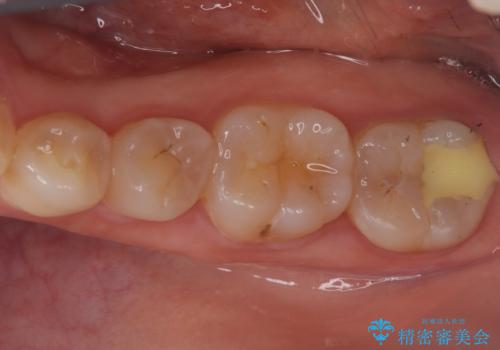

銀歯からセラミックへ。右上奥歯の精密根管治療と審美修復

担当医 河口智英